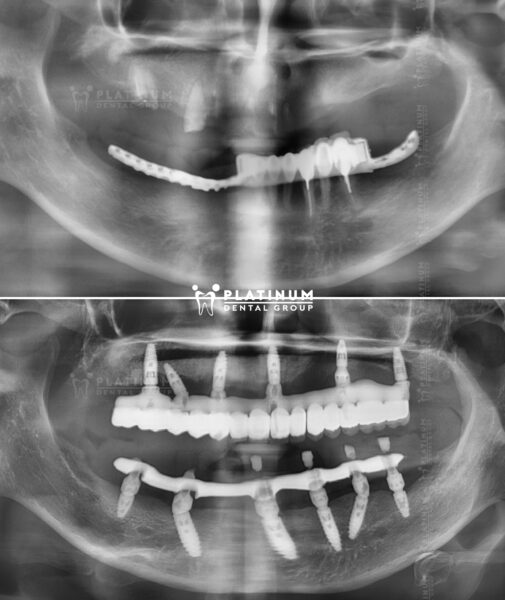

Bạn bị mất răng toàn hàm, hàm trên hoặc hàm dưới và đang lo lắng tìm kiếm các phương pháp điều trị tối ưu. Implant All On 6 mang đến kết quả hoàn hảo về mặt thẩm mỹ lẫn chức năng ăn nhai cho răng đã mất.